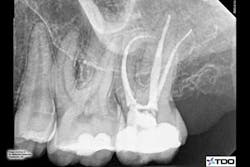

Technique: To navigate a long 90-degree curve, Dr. Behrents took a hybrid approach: ProTaper® Universal files, Lexicon® C-Files, PathFiles, and PROTAPER NEXT™ files.

Dr. Behrents used a ProTaper® Universal S1 shaping file to begin coronal shaping after achieving patency with a #10 Lexicon® C-File. He proceeded through the PathFile® sequence, using all three files to length, and followed with the ProTaper Universal S2 to two-thirds length.

Dr. Behrents then began the PROTAPER NEXT sequence using the X1 and X2 to length in the MB1 and DB canals, while maintaining patency with the #10 Lexicon C-File. Because the MB2 joined the MB1 at midroot, it was instrumented with the X1 only.

He instrumented the P canal using the PROTAPER NEXT X2, X3 and X4. The apical segment of the P canal was finished by hand using a 20/08 GT® hand file.